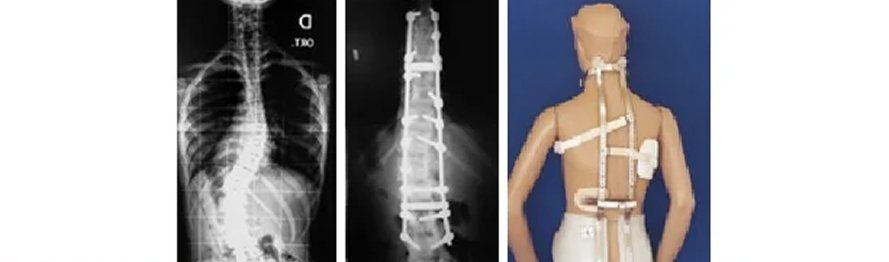

Escoliose é o desvio lateral com rotação de uma série de vértebras, na coluna vertebral. Existem vários tipos (causas) para a escoliose, sendo então necessário a determinação da correta causa para seguir o correto tratamento. O tratamento depende basicamente da idade do paciente e da angulação da escoliose. Pode variar entre uso de coletes até tratamentos cirúrgicos.

Cifose é o nome dado para a curvatura anterior da coluna vertebral, olhando-se em perfil. Hipercifose é o aumento desta curvatura, que pode ocorrer por vários motivos e, ter diferenciados tratamentos.

Existem ainda outras deformidades da coluna vertebral, que também devem ser corretamente avaliadas pelo especialista e tratadas.